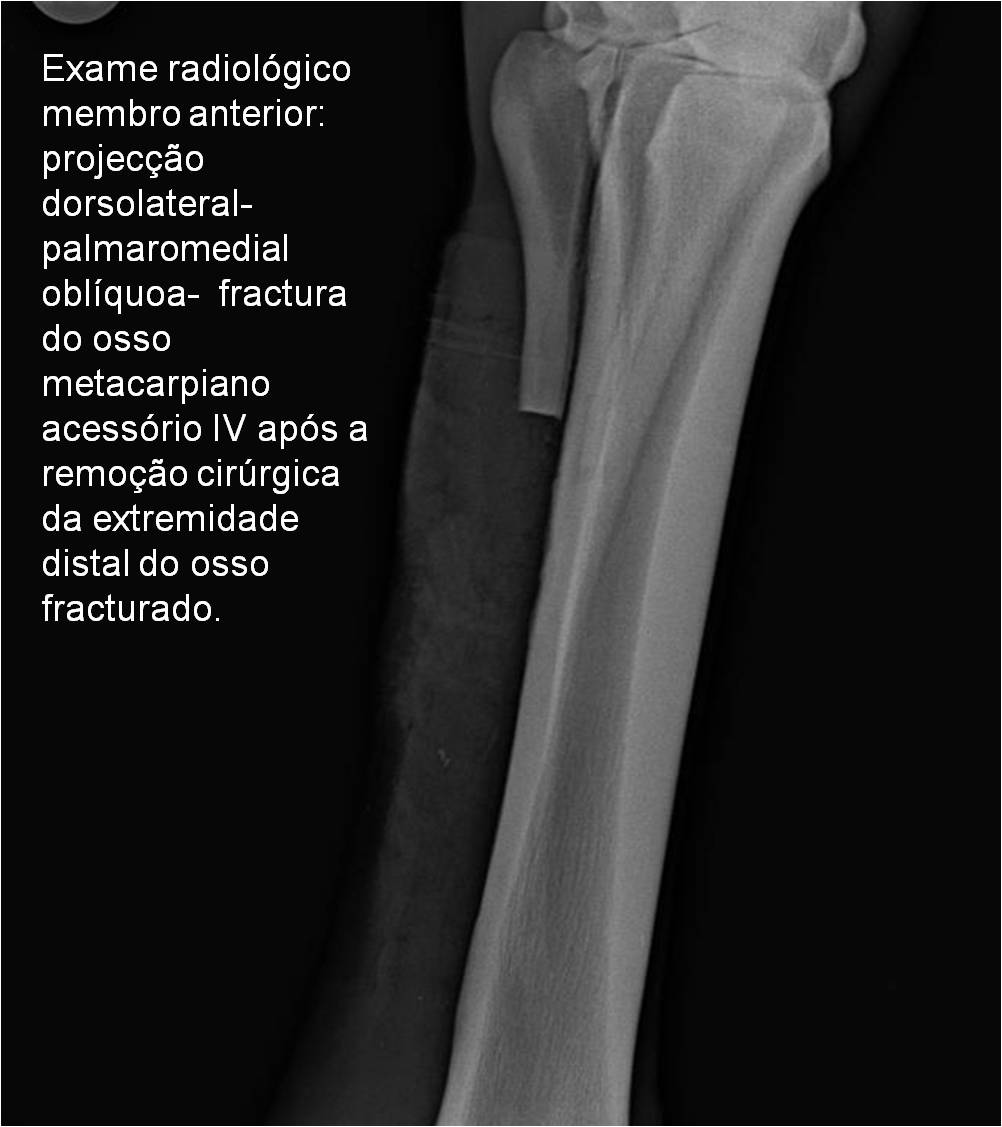

Publisher: Universidade de Évora

Abstract: O relatório de estágio encontra-se estruturado em três partes distintas. A primeira parte faz a caracterização das infraestruturas e funcionamento do Hospital Veterinário de Equinos de Lüsche, Oldenburg, Alemanha, assim como a análise casuística dos casos clínicos acompanhados durante os 6 meses de estágio. A segunda parte consiste de uma revisão bibliográfica sobre quistos do osso subcondral em equinos. Por fim, a terceira parte consta da apresentação e discussão de um caso clínico, nomeadamente o diagnóstico e acompanhamento imagiológico, por ressonância magnética, de um quisto subcondral na terceira falange num cavalo adulto; ### Abstract Equine Practice- Subcondral bone cyst of the third phalanx This internship report is divided in three parts. The first part characterizes the infrastructure and function of the Equine Hospital Lüsche, Oldenburg, Germany, as well as the casuistic of the clinical cases accompanied during the 6 month internship. The second part consists in a bibliographic review of cystic lesions of the subchondral bone in equines. The third part consists in a case report, the diagnostic and imagiological accompaniment, by use of magnetic resonance imaging, of a subchondral bone cyst in the distal phalanx of an adult equine.